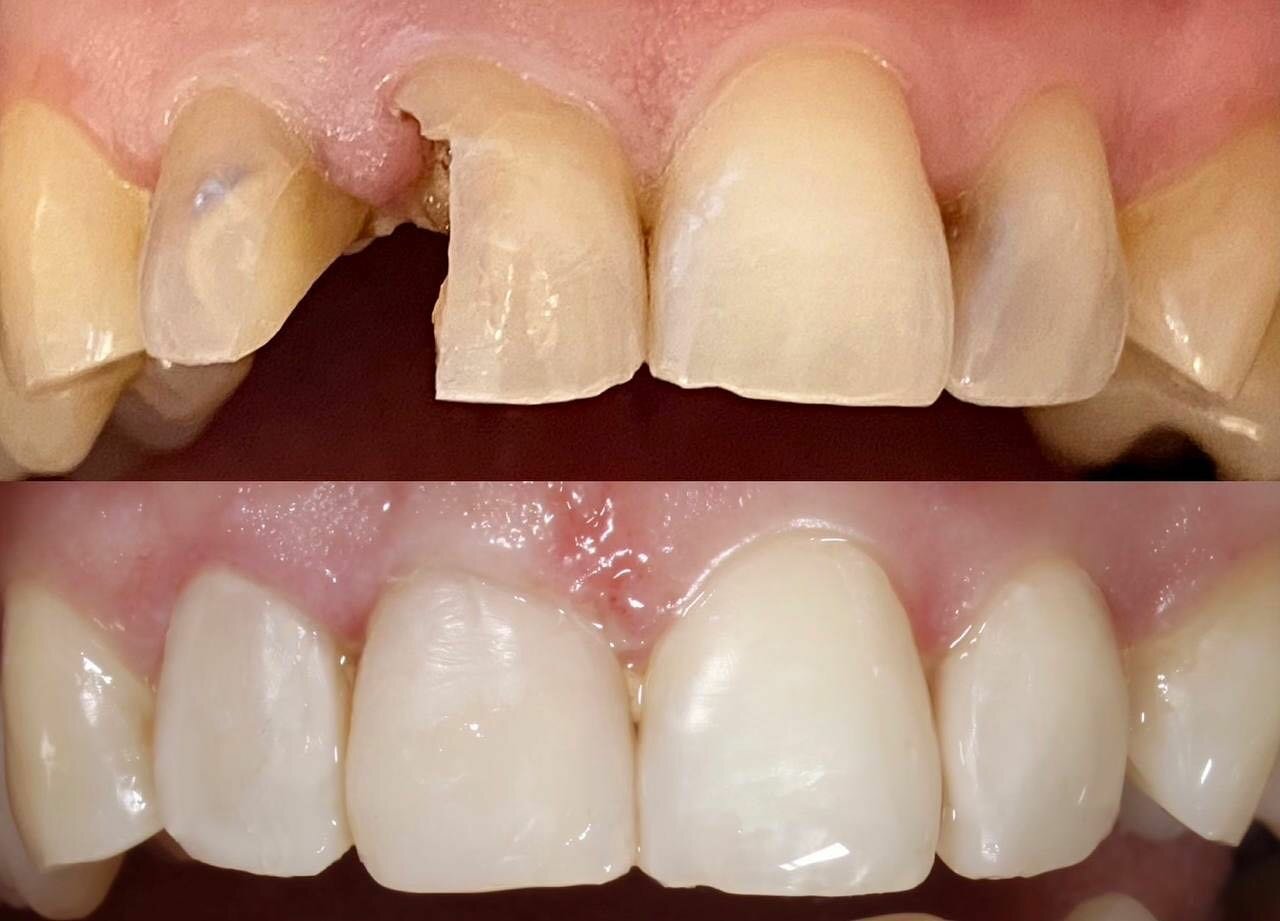

Клиника предоставляет услуги по всем основным направлениям стоматологии, включая общую стоматологию, ортодонтию, хирургическую и эстетическую стоматологию, а также детскую стоматологию. Среди дополнительных услуг: лечение кариеса, пломбирование, удаление зубов, имплантация, протезирование, отбеливание, установка виниров и брекетов, лечение десен и каналов, рентгенография, челюстно-лицевая хирургия и френулопластика.

- лечение кариеса

- Некачественная пломбировка (повреждение нерва).

- Отрицательные последствия лечения (выпадение зубов, испорченный прикус).

Просто отвратительно !!! После лечения зубов у Курбана Алибекова выпали все зубы !!! В место правильного прикуса я удалила все зубы! Не доктор а кошмар !!! Бегите пока не поздно !!! И пациентов лечит в одних перчатках! шок !!!!

‘посчастливилось’ побывать там в ноябре 2022г. Пломбу ставила молодая девушка отвлекаясь на смартфон , радостно делясь видосами с техничкой. Просверлила до нерва, затолкала туда пломбу с усилием. Боль не прошла. Пришлось повторно обратиться с депульпацией уже в другую стоматологию 32 неподалеку, там были очереди, не зря. А в этой шарашкиной конторе нет очередей и если вам только на удаление, то можно сюда.